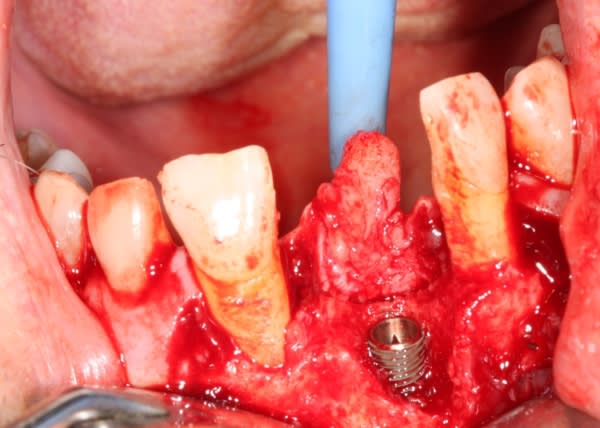

Extraction implantation immédiate mais il y a au moins 7 spires à nue... (photo 1, 2)

dans cette technique un pilier de 2mm de haut est vissé sur l'implant, ce pilier contient un orifice qui permet de transfixer la barre (photo 3,4)

l'espace créé est rempli avec un biomat et le tout est recouvert d'une membrane